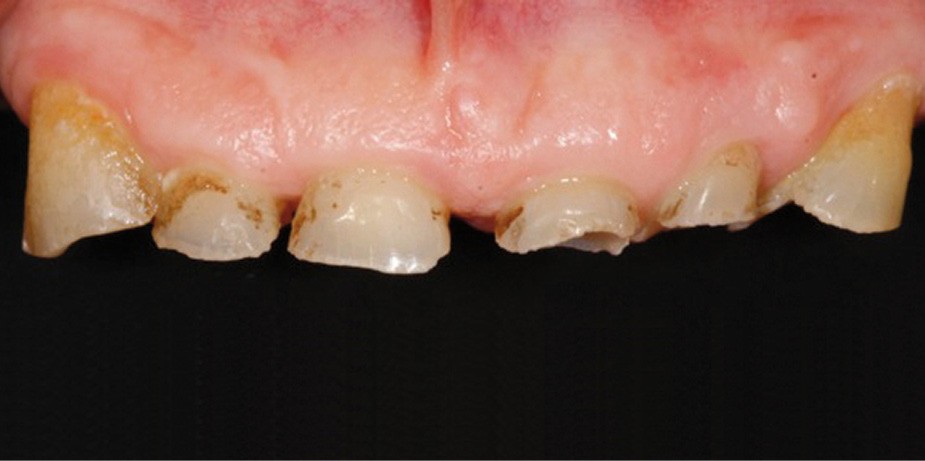

• L’examen intrabuccal montre de nombreux édentements non compensés (14, 15, 16, 24, 25, 26, 27, 47 et 36) ainsi que des pertes de substance très importantes, notamment dans le secteur antérieur.

Une attrition sévère, couplée à une occlusion sans calage postérieur, a engendré des difficultés pour s’alimenter.

• Le bilan esthétique nous indique plusieurs points disgracieux :

– dysharmonie des contours gingivaux (ligne des collets) avec une ligne du sourire basse [1] ;

– perte de substance extrême du bloc incisivo-canin maxillaire et des incisives mandibulaires ;

– visibilité très limitée des dents lors d’un sourire forcé ;

– égressions compensatoires.